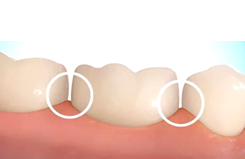

目的2-2「エクストリュージョン」

虫歯で大きく歯質がなくなった時、歯を残すために引っ張り上げる。

虫歯や歯の割れによって、残っている歯が歯肉の中に埋まってしまっている状態の時、被せ物をするのに十分な位置まで、強制的に歯の根を引っ張り出す治療です。歯科医師の教科書的には、歯肉に埋まっていたり、虫歯が歯肉より深い位置に入ってしまっている歯は抜歯することになっていますが、この方法により抜歯せずに歯を残す治療法の一つです。

歯の被せ物を外れにくく、十分な強度にするためには、歯肉の外に出ている健康な歯の高さが最低1mm、可能なら2mm以上必要です。ここが不十分な状態で被せ物をすると、すぐに取れてしまったり、長期的に見ると、歯根に過度の負担がかかり、抜歯が必要な歯根破折につながったりします。